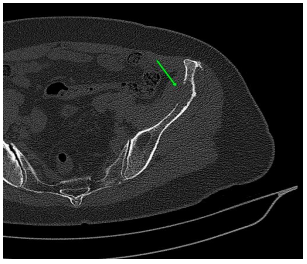

On palpation, there was an 8cm nodule in the right breast and mobile and fibroelastic axillary lymph nodes. There were no palpable nodules in the cervical or supraclavicular region bilaterally. A core needle biopsy was performed with an anatomopathological result of triple-negative grade 2 adenoid cystic carcinoma. Staging demonstrated two 1.1cm pulmonary nodules with soft tissue density suggesting metastasis. Abdominal tomography demonstrated liver nodules suggestive of secondary implants. The PET scan confirmed uptake in the lung and liver nodules, in addition to lytic lesions in S3. Liver biopsy confirmed implantation of adenoid cystic carcinoma. The patient was staged as T2N0M1. Chemotherapy was started with a regimen of Carboplatin, Paclitaxel and Pembrolizumab. After the third cycle of chemotherapy, the breast was reevaluated without showing any tumor reduction. The metastases also did not regress, and treatment was interrupted. The patient evaded the service until he returned in January 2024 complaining of pain in his right hip and difficulty walking. Chest and hip tomography showed an increase in lung lesions and the appearance of lytic metastasis in the iliac bone (figure 1, 2, 3).

Figure 3: